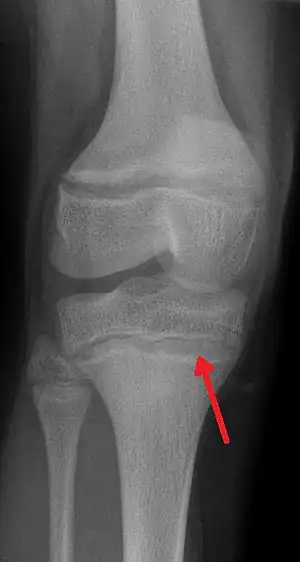

| An X ray demonstrating the characteristic finding of lead poisoning in humans—dense metaphyseal lines. | |

Blood lead levels are an indicator mainly of recent or current lead exposure, not of total body burden.[173] Lead in bones can be measured noninvasively by X-ray fluorescence; this may be the best measure of cumulative exposure and total body burden.[23] However this method is not widely available and is mainly used for research rather than routine diagnosis.[87] Another radiographic sign of elevated lead levels is the presence of radiodense lines called lead lines at the metaphysis in the long bones of growing children, especially around the knees.[174] These lead lines, caused by increased calcification due to disrupted metabolism in the growing bones, become wider as the duration of lead exposure increases.[174] X-rays may also reveal lead-containing foreign materials such as paint chips in the gastrointestinal tract.[18][174]